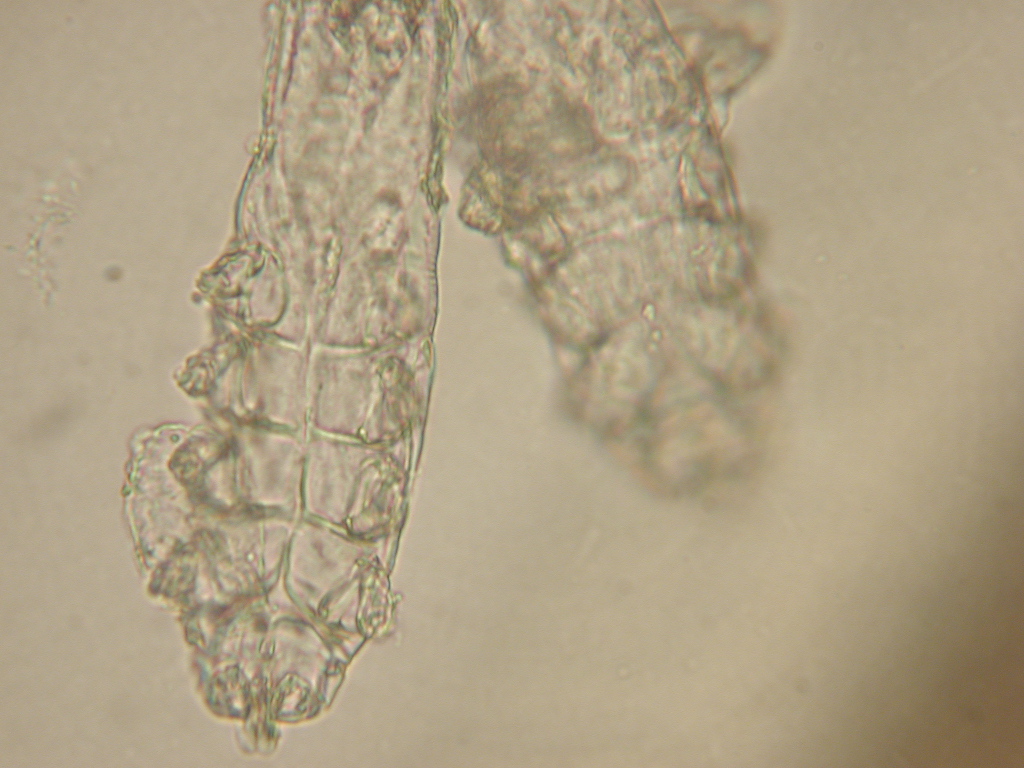

Update on new therapies for demodicosis

Efficacy and safety of sarolaner against generalised demodicosis in dogs in European countries – a non -inferiority study Becskei, B et al Vet Derm 29, 3. 203-207 2018